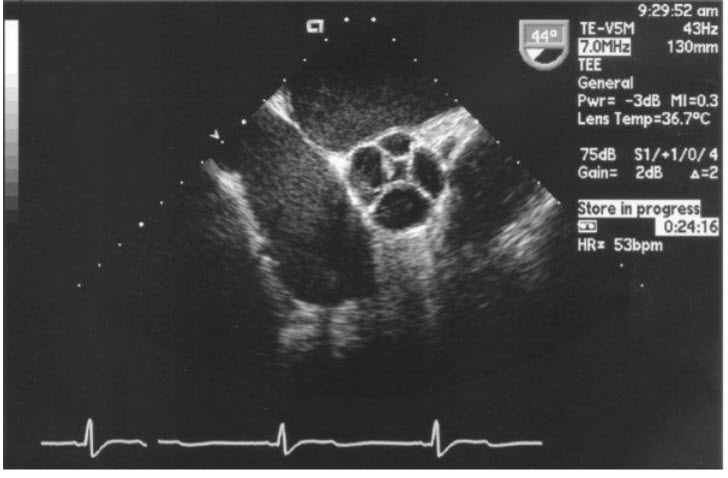

Figure b. A magnified TEE long-axis view of the LVOT, aortic valve, and ascending aorta. There is a membrane visible in the LVOT, consistent with a subaortic membrane.